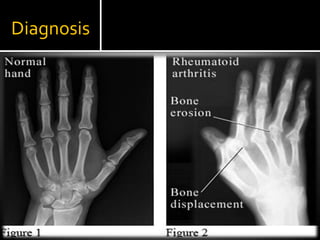

Diagnosis

At least FOUR criteria MUST be met for classification of RA.Morning stiffness of more than 1 hour most mornings for at least 6 weeks.Arthritis and soft-tissue swelling of more than 3 of 14 joints, present for at least 6 weeks.Arthritis of the hand joints, present for at least 6 weeks.Symmetric arthritis, present for at least 6 weeks.Subcutaneous nodules in specific places.Rheumatoid Factor at a level above the 95th percentile.Radiological changes suggestive of joint erosion.

X RaysX rays of hands and feet are generally performed in people with RA.Magnetic Resonance Imaging (MRI)Ultrasounds